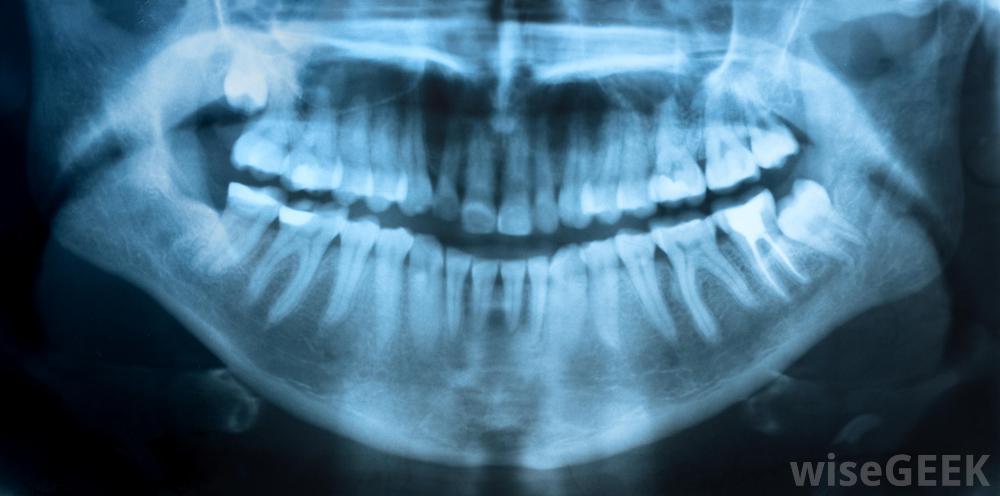

X光是临床牙科的一个组成部分临床牙科医生也强调维护健康的牙齿。因此,许多牙科诊所为病人提供清洁牙齿的服务。员工还教育病人正确的自我护理程序,如使用牙线和刷牙牙齿。如果临床医生发现患者的牙齿弯曲或间距过大或咬合不正,可将患者推荐给另一个临床牙科分科医生:正畸医师。